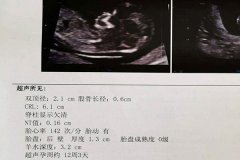

再次怀孕需早期超声确认孕囊位置,排卵试纸监测结合基础体温记录能精准把握受孕时机。

有过宫外孕史的孕妇需在停经35天左右进行阴道超声排查,hCG翻倍情况要密切跟踪。